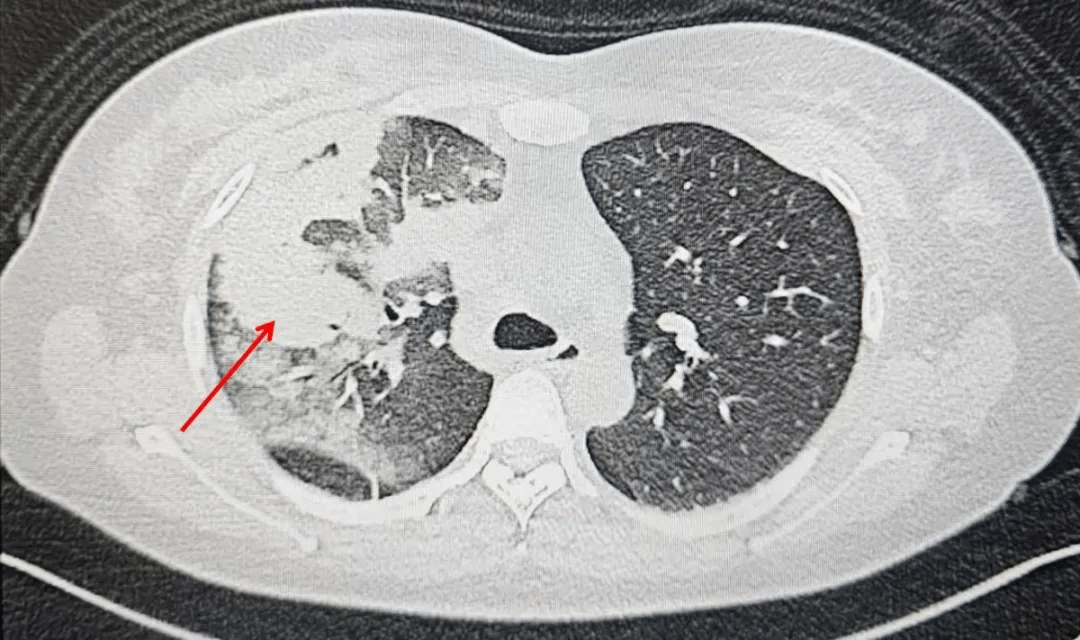

一周前,李女士因无明显诱因出现发热、咳嗽、咳痰,自行服药后症状不见好转,来到西安市第九医院呼吸与危重症医学科就诊。这一查不要紧,胸部CT显示:左肺上叶及中叶多发高密度影! 这样的影像学表现绝非普通感冒那么简单。

入院时胸部CT,左肺上叶及中叶多发高密度影